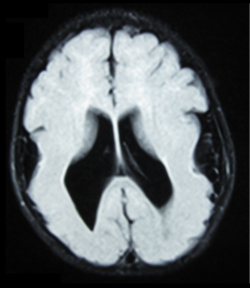

A brain MRI showing lissencephaly (smooth brain) with ventriculomegaly.

MEB can be diagnosed with medical imaging by the shared patterns of brain structural abnormalities. Common practice includes magnetic resonance imaging (MRI) and computerized tomography (CT). They can show the enlargement of ventricle, absence or degeneration of septum pellucidum, pachygyric symptoms, abnormalities in corpus collosum, lissencephaly.[21] Fetal MRI and ultrasound are used as a prenatal diagnostic tool if needed to screen for the disease. Observation like general structural malformation in the third trimester suggests congenital muscular dystrophy.[22] Further diagnostic test is required to make confirmation.

Clinically, MRI is preferred over CT scan for its ability to reveal the neuron migration more precisely.[21] The result obtained from CT scan is limited to the size of ventricles and location of white matter whereas only MRI can provide information on cortical problems.